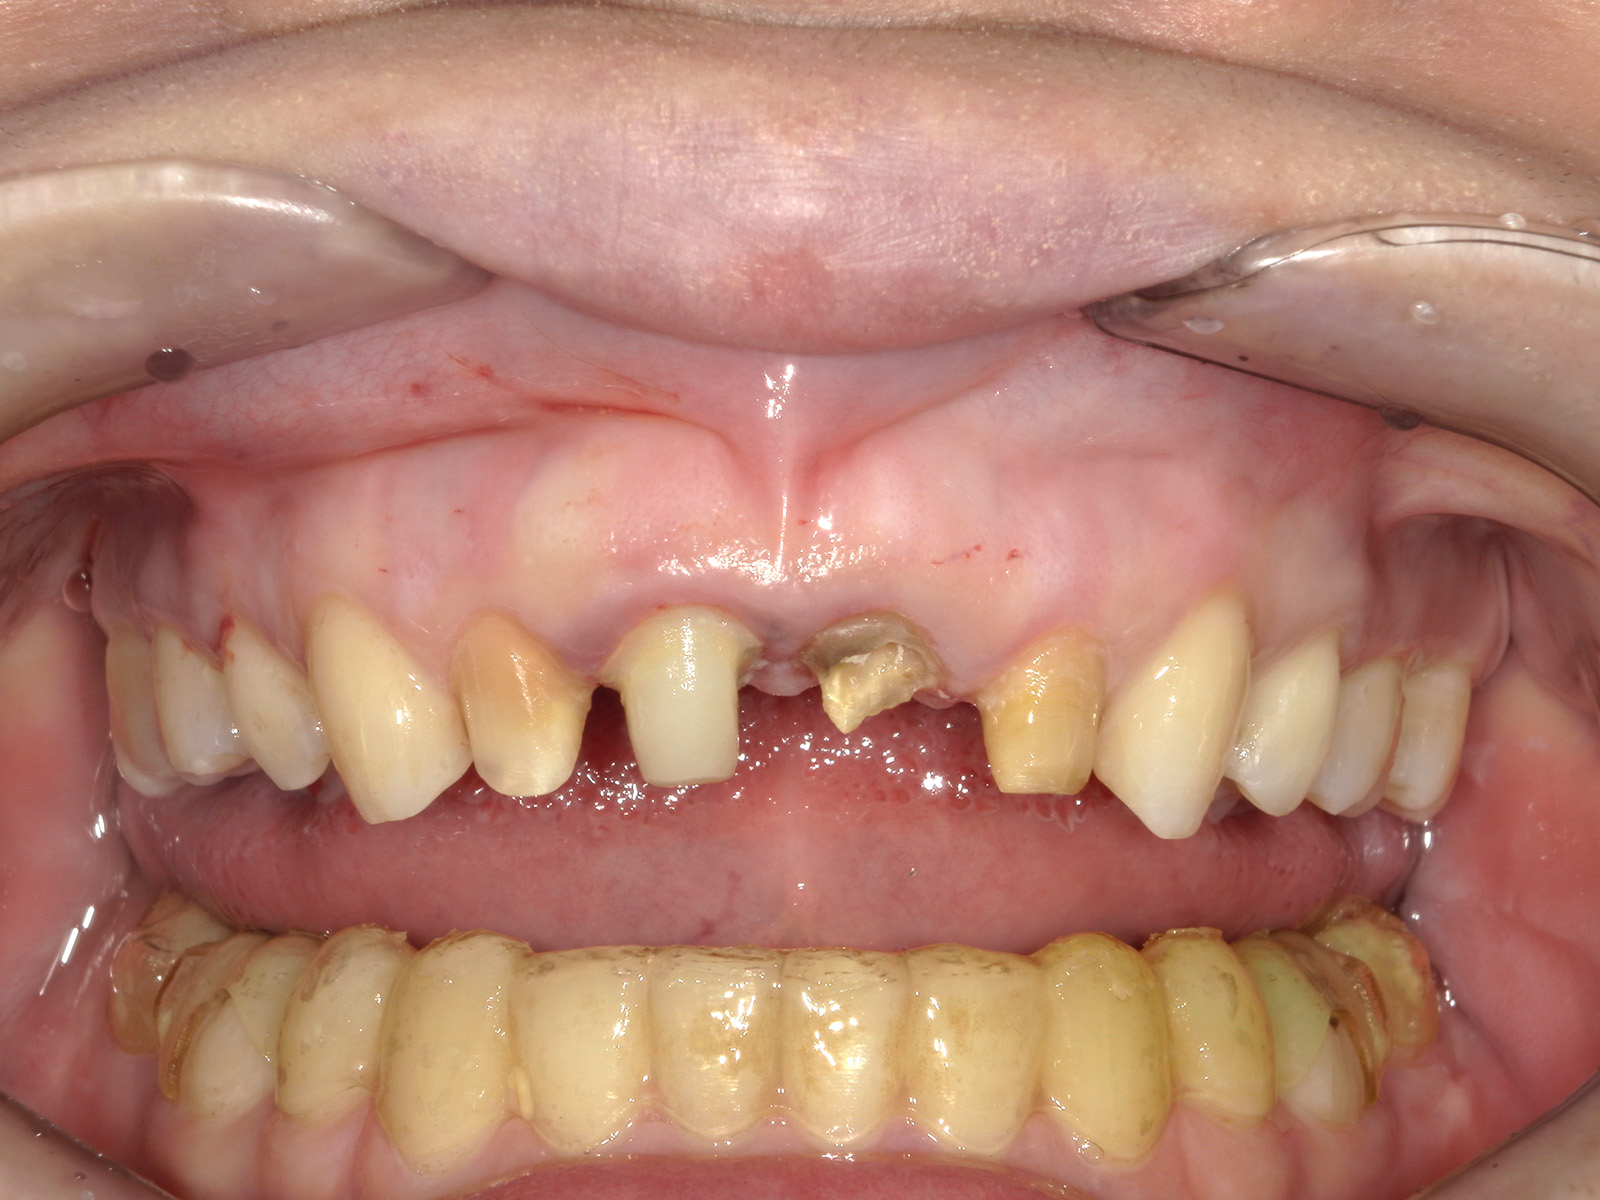

被せ物を安定させる「クラウンレングスニング」

歯が大きく欠け、根だけが残った状態では、被せ物の装着が難しくなります。

このような場合に行うのが「クラウンレングスニング」です。

歯茎や周囲の骨を丁寧に削り、歯の根を十分に露出させることで、被せ物を安定して装着できるようにします。

歯の保存を第一に考える治療の一つです。

歯肉を切開し、歯根を露出させた状態。